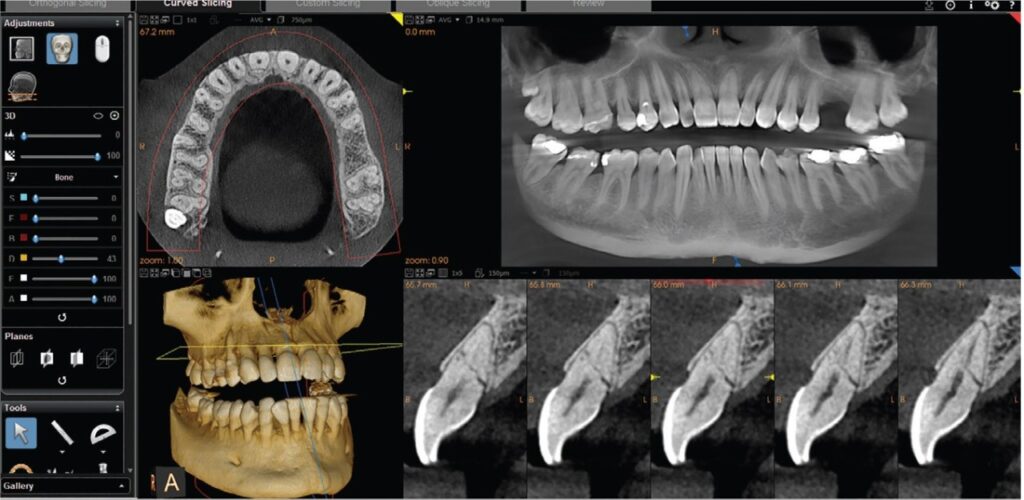

This provides a highly detailed, clear image of the teeth and jaw. It allows us to identify issues that may not be visible on a standard X-ray.